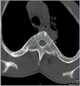

Spondylocostal dysostosis, also known as Jarcho-Levin syndrome (JLS), is a rare, heritable axial skeleton growth disorder. It is characterized by widespread and sometimes severe malformations of the vertebral column and ribs, shortened thorax, and moderate to severe scoliosis and kyphosis. [Source: Wikipedia ]

Ribbon-like ribs

Thin ribs

Wavy ribs